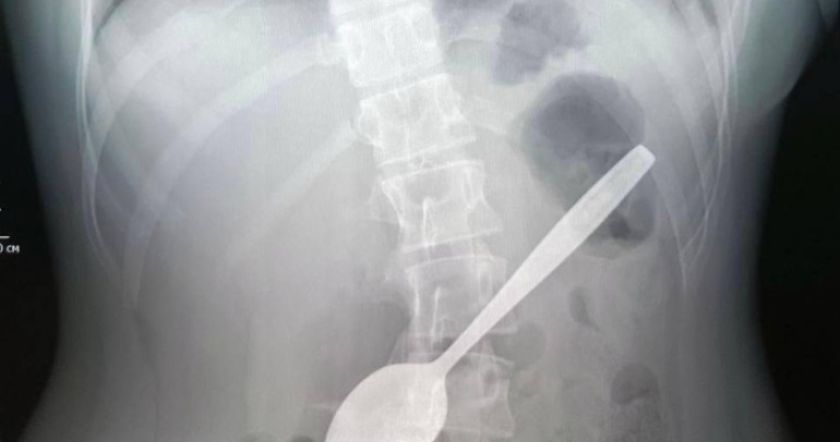

«Ռոշալի անվան մանկական կլինիկական կենտրոն է ընդունվել 14-ամյա մի աղջիկ, որը պատահաբար կուլ էր տվել գդալը: Նա փորձում էր կոկորդում մնացած խնձորի կտորը դուրս բերել: Բժիշկներն անմիջապես որովայնի օրգանների ռենտգեն են կատարել և հաստատել օտար մարմնի առկայությունը աղջկա ստամոքսում», - ՌԻԱ Նովոստիի փոխանցմամբ՝ ասված է հաղորդագրությունում:

Էնդոսկոպիստ Դարիա Ստեպանենկոն հայտնել է, որ վիրահատությունը տեւել է մոտ մեկ ժամ և հաջող է անցել։